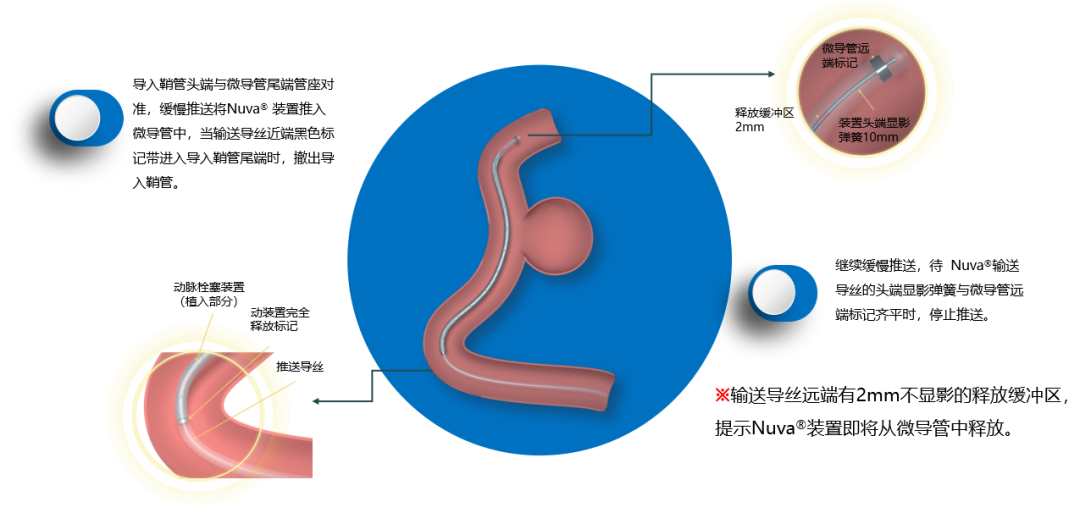

操作步骤1:微导管到位

操作步骤2:Nuva®输送到位

操作步骤3:Nuva®远端定位

操作步骤4:Nuva®释放(1)

Nuva®释放的关键是保证张力的释放和平衡,以实现装置顺利打开并与血管完美贴壁。

当输送导丝上的释放显影区间标记末端到达微导管远端标记时,Nuva®已经到达可回收的极限位置,即超出微导管远端标记时,Nuva®将不可再进行回收。

释放进入尾部释放阶段,该阶段在微导管中的长度约5mm~8mm;当输送导丝完全释放标记超出微导管远端标记时,Nuva®完全释放。